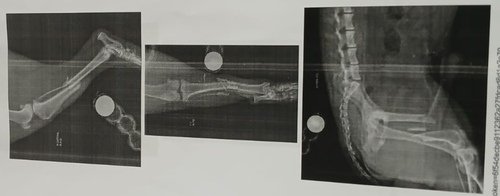

Um cãozinho muito dócil que foi atropelado e está com as duas patinhas traseiras fraturadas, necessitando urgentemente de cirurgia, correndo risco do osso perfurar Nick.